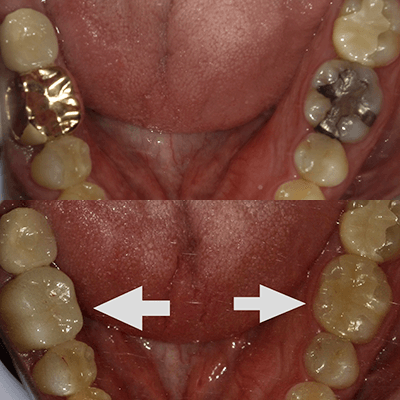

銀の詰め物で再発しやすいと言われる理由

保険診療で一般的な銀色の詰め物(いわゆる銀歯:金銀パラジウム合金など)は、もちろん適切に入っていればすぐに問題が起こるわけではありません。ただ、臨床では「古い銀歯の下で二次虫歯が進んでいた」というケースがかなりの頻度で経験します。

理由1:境目に“わずかな変化”が起きやすい

歯は噛むたびにたわみ、長い年月で少しずつすり減りも起こります。一方で金属は歯と性質が異なるため、噛む力や温度変化などの影響で、境目に微細な段差やすき間が生じることがあります。そこに細菌や汚れが停滞すると、再発リスクは高まります。